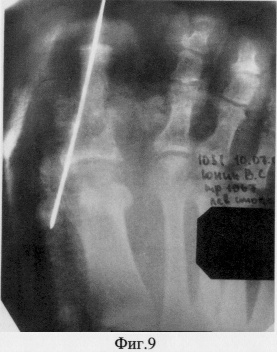

После чего кровоснабжаемый костный трансплантат телескопически внедрен в основание основной фаланги первого пальца и фиксирован спицей, а кожно-фасциальный лоскут подшит к краям дефекта покровных тканей по периметру (фиг.8, 9).